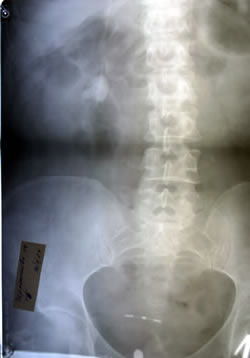

ОБЗОРНАЯ

УРОГРАФИЯ: |

|